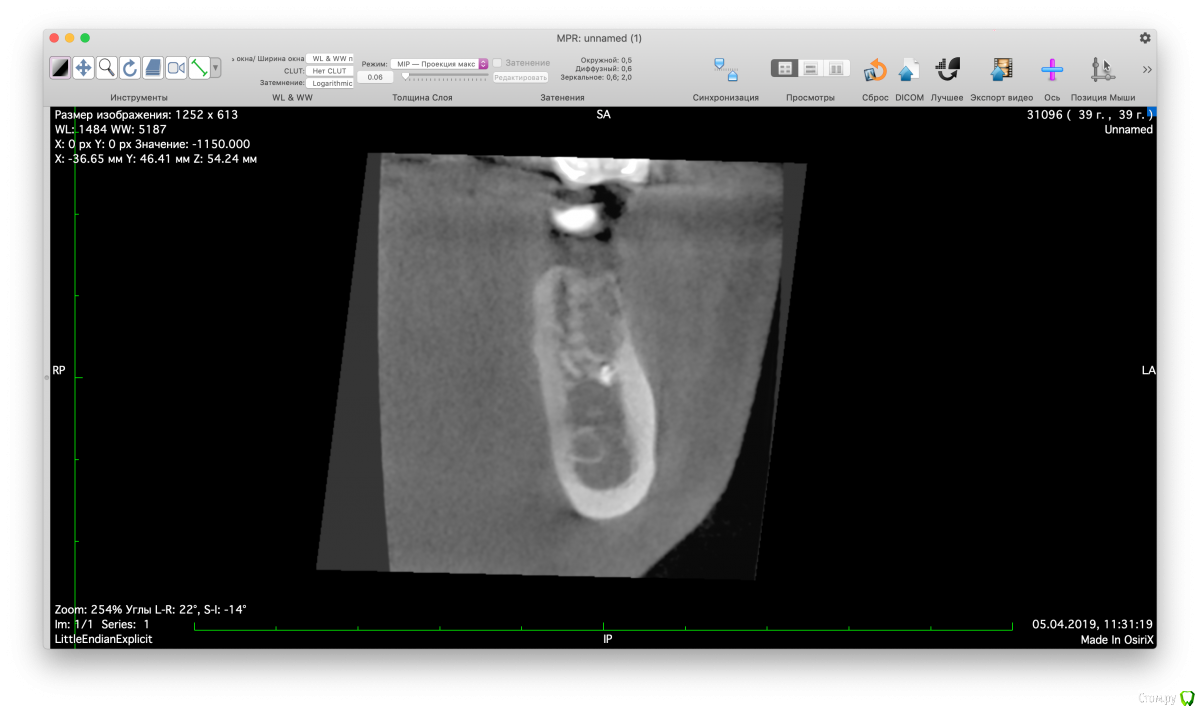

Valerkaa Опубликовано 15 мая, 2019 Поделиться Опубликовано 15 мая, 2019 Добрый день, коллеги. Только начинаю свою работу в сфере имплантации. Планируется имплантация в области отсутствующего 3.6, меня смущает наличие ранее выведенного пломбировочного материала. Понимаю, что при формировании ложа под имплантат материал фрезой не удалится, смущает просто само наличие материала вблизи будущего имплантата. Доставать или оставить все как есть? Заранее спасибо. Ссылка на комментарий

Valerkaa Опубликовано 15 мая, 2019 Автор Поделиться Опубликовано 15 мая, 2019 Имплант должен стать мезиальнее.конечно, просто смущает само наличие материала рядом Ссылка на комментарий